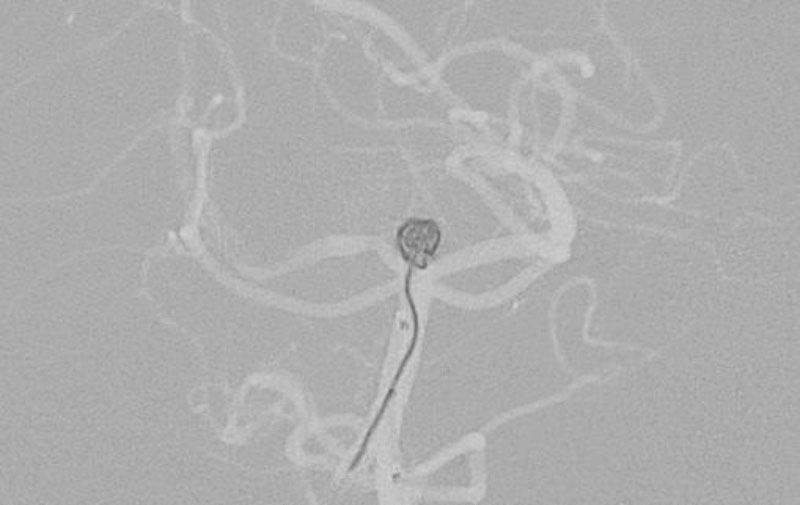

No.1628 手術前

No.1628 手術中

No.1628 手術後